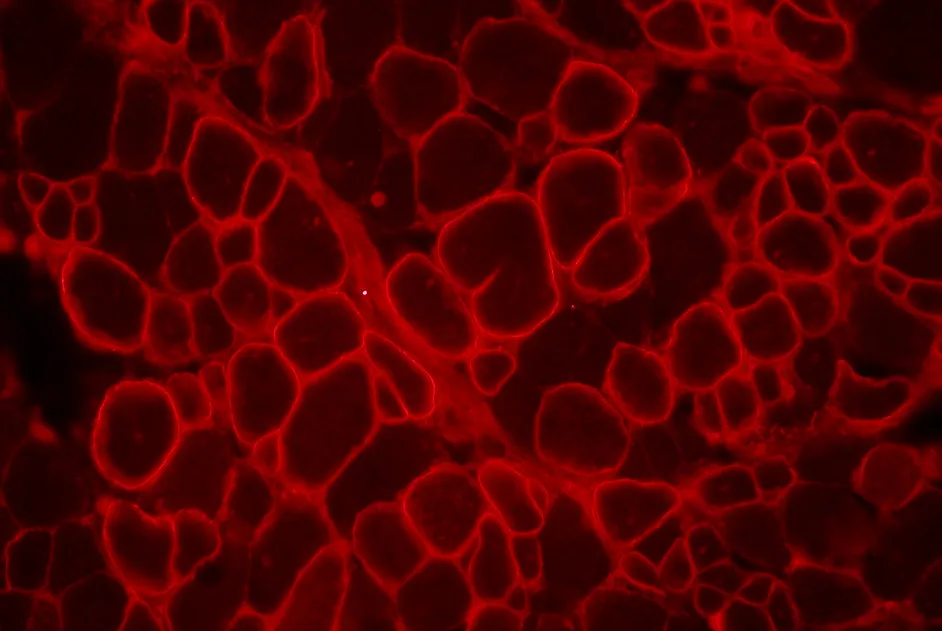

Le trans-épissage s'avère être une stratégie alternative efficace pour les personnes atteintes de DMD chez lesquelles le saut d’exon ne peut pas être appliqué.